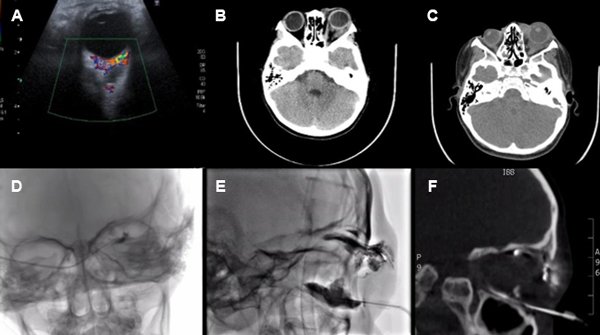

Se examinaron en el servicio 14 pacientes con patología vascular de compromiso orbitario y/o palpebral (tabla 1). De ellos, tres fueron hemangiomas infantiles (HI) (fig. 1), todos de sexo femenino tratados con betabloqueantes; seis malformaciones linfáticas con marcado predominio de sexo femenino, la mayoría tratados con escleroterapia guiada por control radiológico, al igual que los cuatro casos de malformación venolinfática, y un caso de fístula carótido-cavernosa de alto flujo, tratada con embolización. Necesitaron retratamiento por recidiva 3 malformaciones venolinfáticas y 1 linfática pura. El rango etario de aparición de signos clínicos fue desde el nacimiento hasta los 12 años, con una media de 3,6 años y una mediana de 1,67 años, pero característicamente los HI se manifestaron en una edad promedio de 1 mes de vida, mientras que en las malformaciones vasculares fue de 4,5 años. El signo oftalmológico más manifiesto fue la proptosis (8 casos), seguido por el estrabismo (6 casos). La localización más común fue órbita con asociación a párpado inferior. Hubo 5 casos con hallazgos vasculares asociados extra-orbitarios/palpebrales. La amplia mayoría de casos obtuvo una resolución clínica de su cuadro de base (93%). Dentro de los métodos de imágenes más utilizados se encontró en primer lugar la ecografía (78%), seguido por la resonancia magnética (64%). En las figuras 2 y 3 se presentan dos casos y los estudios descriptos y la escleroterapia guiada bajo control radiológico.

Figura 3. Paciente con malformación linfática orbitaria tratada con esclerosante. Patología asociada: microftalmía, leucoma, atrofia iridiana. A) Ecografía Doppler color, imagen orbitaria. B y C) Tomografía computada en corte sagital. D, E y F) Procedimiento de escleroterapia realizada bajo control radiológico.